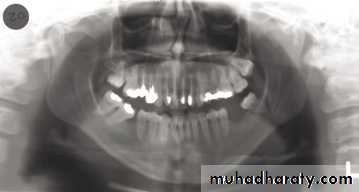

( hyoid bone, the hard palate, epiglottis).A dental panoramic tomograph showing the main real hard tissue shadows, including the plastic head support, drawn in on one side of the radiograph, NS — nasal septum,

MIT — middle and inferior turbinates, O — orbital margin, HP — hard palate, A — floor of antrum, Z — zygomatic arch, EAM — external auditory meatus, MP — mastoid process,

SP — styloid process, H — hyoid, P — plastic head support.